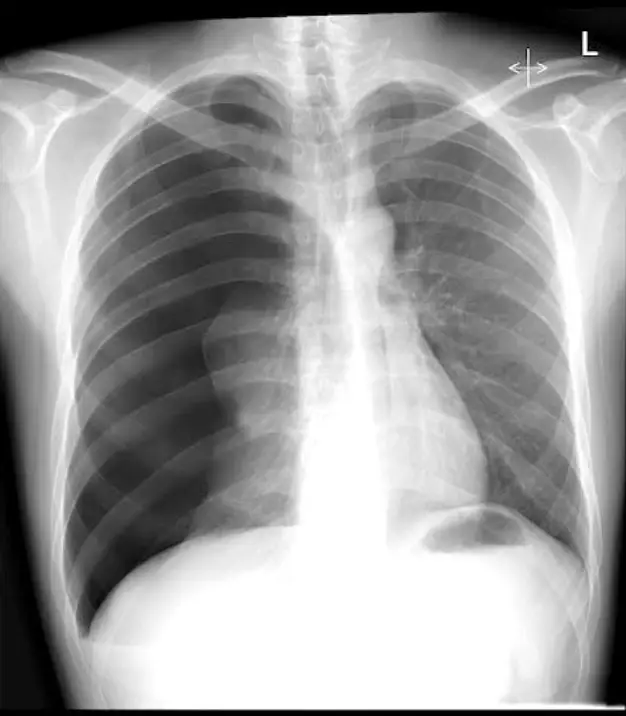

一位25歲男性因呼吸困難至急診就醫,主訴2天前工作撞擊到右側胸部,胸部X光檢查如圖(三),下列處置何者較適當? 圖片描述

從正面胸部 X 光可見:

1. 右側整片肺野呈高度透亮,幾乎無血管紋理,顯示大量自由空氣充斥右胸腔。

2. 右肺實質在肺門周圍可見一條皺縮的肺邊緣,代表肺實質已高度萎縮。

3. 心臟與縱膈向左側偏移,氣管亦被推向左側,提示胸腔內壓力升高造成縱膈位移。

4. 右橫膈明顯較左側低,並呈「deep sulcus sign」輪廓,符合張力性氣胸的典型 X 光表現。 綜合判斷:影像高度支持右側 tension pneumothorax。

1. Tension pneumothorax 影像特徵:單側肺透亮、肺紋理消失、縱膈與氣管偏移、橫膈下移或 deep sulcus sign。